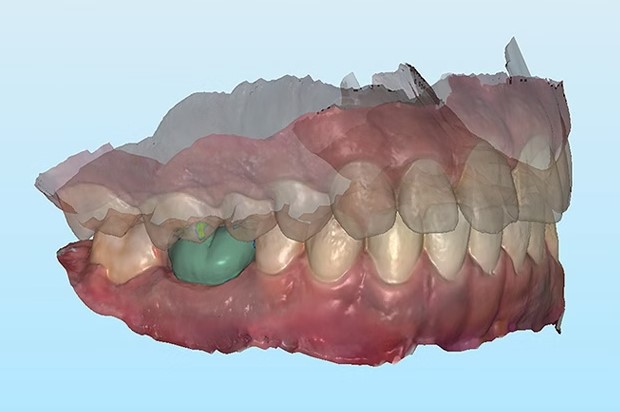

修复手术案例研究之一。图片来自自然。

修复手术案例研究之一。图片来自自然。